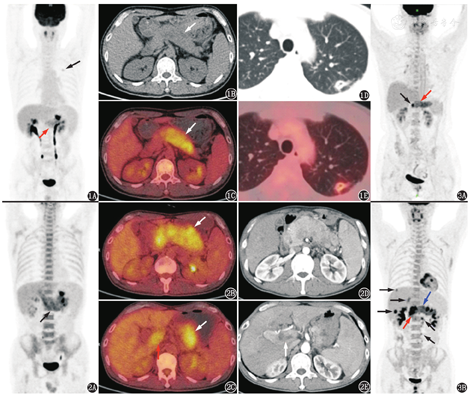

患者男,41岁,主诉消瘦3个月,否认腹痛、腹泻、恶心、呕吐、黄疸、发热、乏力、盗汗等症状。腹部超声见胰腺弥漫性肿胀,体尾部较明显,胰腺体尾部回声减低。腹部增强CT见胰腺体尾部形态饱满,体尾部大片低密度影。血清CA19-9 55.27 (0~37) kU/L,IgG4正常。外院行超声内镜下胰腺穿刺活组织检查,病理结果:有少量退变上皮细胞,未见恶性肿瘤细胞。18F-FDG PET/CT图像(图1)上可见胰腺弥漫增粗,体尾部较明显,呈"腊肠样改变" ,胰腺自胰颈部至胰尾代谢弥漫均匀增高,SUVmax 3.5。此外,左肺上叶可见代谢轻度增高的小空洞,SUVmax 2.1,纵隔窗见洞壁钙化灶;双肺内另有散在硬结灶,代谢不高。随访观察5个月后复查的PET/CT图像见图2。

胰腺肿瘤表现为弥漫性病变(代谢增高)的情况并不多,主要考虑2种情况:第1种是胰腺头颈部肿瘤因阻塞胰管等引起远端胰腺组织急慢性炎性反应,即肿瘤所致胰腺炎(tumor-induced pancreatitis),这种情况相对更多见,比如图3中2个病例,分别是胰头部和胰颈部导管腺癌伴远端胰腺组织弥漫性炎。这2个病例中胰腺头颈部的肿瘤病灶代谢更高,与远端体尾部的炎性反应容易区分,但若是FDG代谢不那么高的胰腺癌,鉴别起来难度就更大,这时可以通过腹部增强CT或MR观察胰腺近端有无占位,远端胰管有无扩张,还可通过延迟显像来进一步判断近端占位与远端胰腺炎有无代谢上的差异。

本例中,患者主诉为消瘦、血清CA19-9轻度升高而IgG4正常,不支持AIP的诊断,但超声内镜穿刺组织检查阴性,未能明确诊断。进行随访观察,5个月后患者仍有体质量持续性下降,复查PET/CT及增强CT(图2)。PET/CT见胰腺肿胀较前更明显,并且形态不规则,代谢也更高,SUVmax 4.3,还出现门静脉主干内代谢增高区,先前的左肺结节在抗生素治疗后消失;腹部增强CT也见胰腺明显肿胀,强化不均匀,门静脉主干及肝内主要分支充盈缺损,考虑胰腺恶性病变伴门静脉癌栓。之后患者再次行超声内镜下穿刺活组织检查,诊断为胰腺腺泡细胞癌,过碘酸希夫(periodic acid Schiff, PAS)染色(+);免疫组织化学检查:抗胰糜蛋白酶(+),抗胰蛋白酶(+),细胞角蛋白单克隆抗体AE1/AE3(+),CD56(-),嗜铬粒蛋白(-),突触素(-),细胞增殖核抗原Ki-67指数35%。